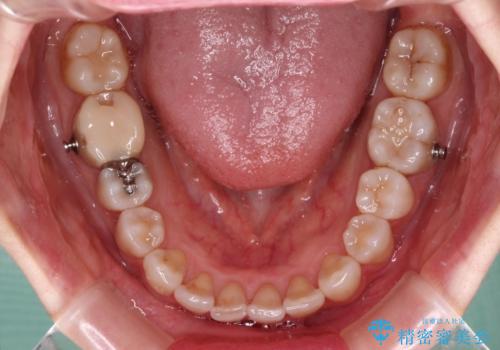

- インビザライン

骨格的な左右差があったため、上下の正中を合わせることができませんでした。

骨格の差は改善できないため、奥歯の咬み合わせに物足りなさを感じましたが、奥歯の咬み合わせによる不自由はなく、口元の突出感も改善することができました。